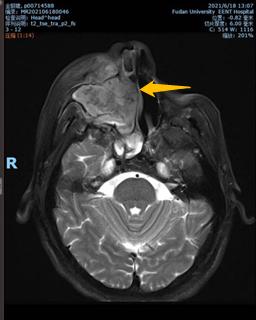

磁共振(MRI)检查结果图示而这次因身体不适来院就诊的结果,对J先生而言犹如晴天霹雳。磁共振显示右侧上颌窦充满了肿瘤组织,肿瘤还向周围结构扩展,侵犯了筛窦、眼眶底部、牙槽、硬腭、软腭、翼腭窝、面颊部皮肤,已丧失了彻底手术切除的机会。